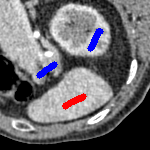

The motivation for this work comes from observing contradictions in using piecewise-constant intensity fitting terms in selective segmentation. Whilst good results are possible with this approach, the exceptional cases lead to severe limitations in practice. This is quite common in medical imaging as demonstrated in Fig. 1, where the target foreground has a low intensity. Given that the corresponding background includes large regions of low intensity, the optimal average intensities for this segmentation problem are and . For cases where , we see that by (1), almost everywhere in the domain . This means that it is very difficult to achieve an adequate result, without an over-reliance on the user input or parameter selection.

for and as defined in (33). This is consistent with respect to the intensities of the observed object and the concept of selective segmentation. In Fig. 3 we see the difference between CV and the proposed fitting terms for given user input on a CT image. For the CT image, the CV fitting terms are near 0 within the target region. This is despite there being a distinct homogeneous area with good contrast on the boundary. This illustrates the problem we are aiming to overcome. With the proposed fitting term this phenomenon should be avoided in cases like this. By defining as in (33) there is no contradiction if the foreground and background intensities of the target region are similar.